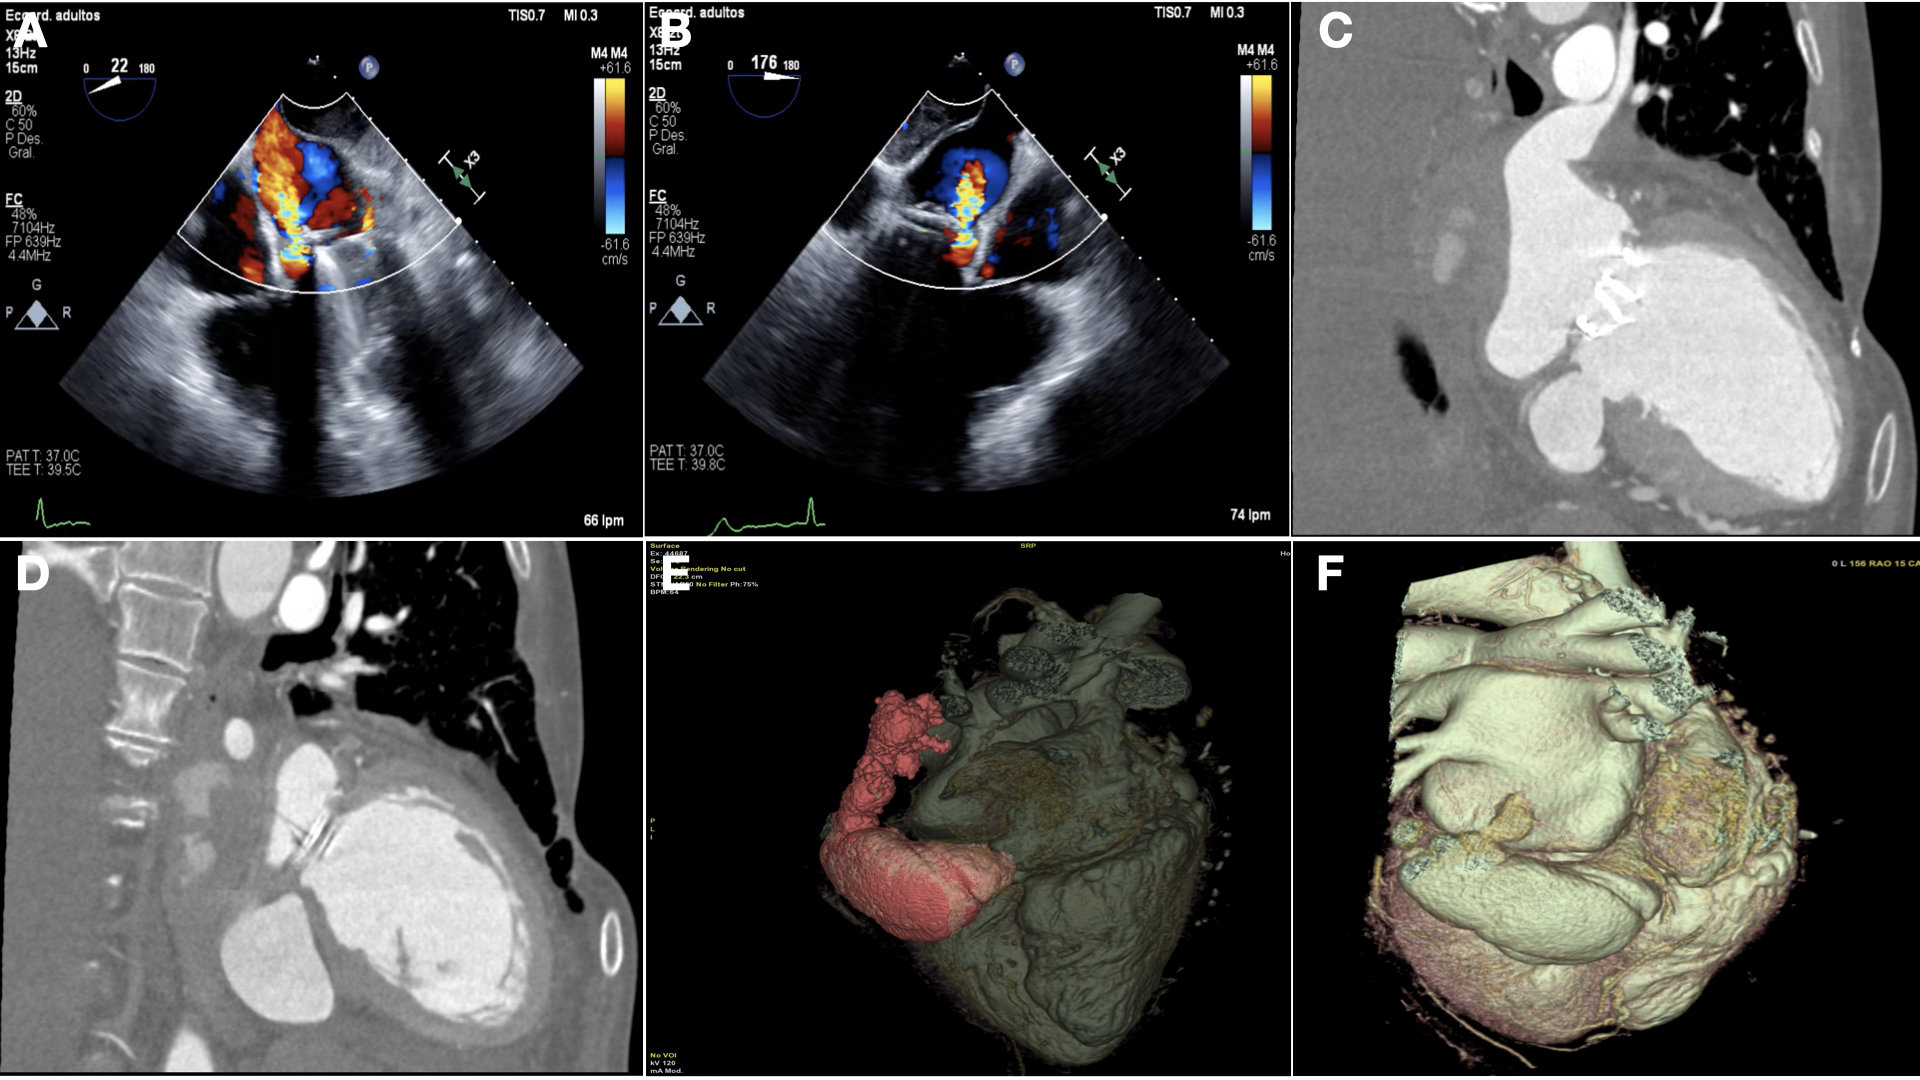

One-year postoperative, the patient remains asymptomatic with mild aortic regurgitation and significant size reduction of the pseudoaneurysm (Figure 3A-D; Video 2).